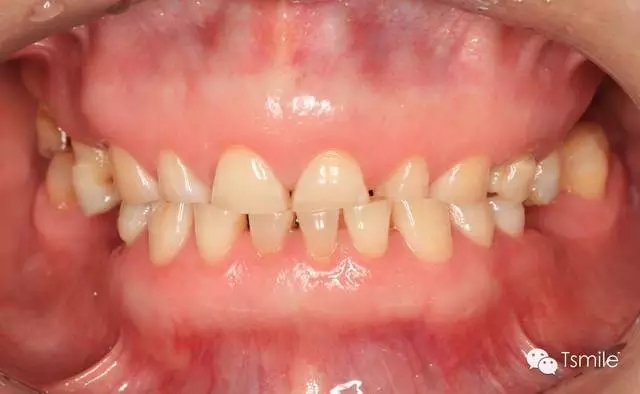

圖1: 夜磨牙導(dǎo)致的牙列重度磨耗

磨耗是指在下頜的功能運(yùn)動(dòng)(咀嚼食物等)或副功能運(yùn)動(dòng)(夜磨牙、緊咬牙等)過程中上下頜牙齒和牙齒之間的機(jī)械摩擦而導(dǎo)致的牙齒表面硬組織的缺損。

磨耗患者一般有特定的飲食習(xí)慣,如喜吃硬食、嚼檳郎等,這些飲食習(xí)慣導(dǎo)致咀嚼時(shí)咬合力過大,或者牙齒咬合面之間粗燥的事物導(dǎo)致牙面承受過度的機(jī)械摩擦;磨耗患者一般還有夜磨牙、緊咬牙等副功能運(yùn)動(dòng)病史。